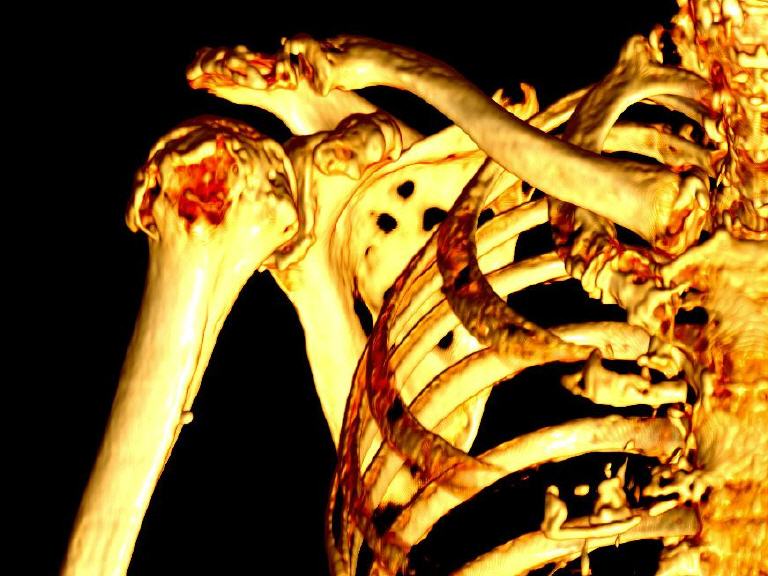

Die Röntgenreizbestrahlung ist eine spezielle Therapieform, bei der schwache Röntgenstrahlen gezielt eingesetzt werden, um schmerzhafte Entzündungen, wie z. B. bei Arthrose, Sehnenreizungen oder einen Fersensporn, zu behandeln. Die Strahlen wirken entzündungshemmend und schmerzlindernd, ohne das umliegende Gewebe stark zu belasten. Die Behandlung ist schmerzfrei, dauert nur wenige Minuten und erfolgt in mehreren Sitzungen. Die Strahlendosis ist dabei sehr gering, sodass die Therapie gut verträglich ist.

- Röntgenbestrahlung der Knochen, Bänder und Gelenke.